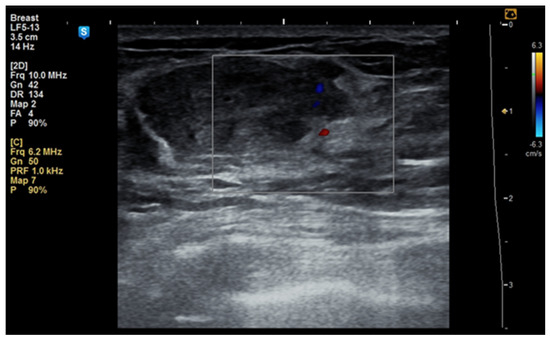

Although the literature identifies mammography as the primary diagnostic method for breast hamartomas, in our study, the diagnosis was established via ultrasound examination. This preference is due to the younger age of many patients, with only three being over 50 years old. On ultrasound, hamartomas typically appear as oval, well-circumscribed masses with heterogeneous hypoechoic or isoechoic echostructures and reduced or absent vascularity (Figure 1 and Figure 2). In our study, the concordance between ultrasound and histological size was 84.61%. Preoperative ultrasound diagnosis of hamartoma was established in only five patients, representing 38.46% of the cases.

During the study period, a case initially suspected to be a hamartoma on MRI, with peripheral vessel involvement and benign axillary adenopathy, was encountered. However, an ultrasound examination established the diagnosis of a 5 × 3 cm lipoma in a 52-year-old woman, despite the tumor’s rapid growth over the course of one year (Figure 4a,b). The lipoma consisted solely of homogeneous adipose tissue, appearing hypoechoic on the ultrasound exam, with few thin striations. This case is particularly significant as it highlights the diagnostic challenges associated with differentiating between breast hamartomas and lipomas, especially in instances where rapid tumor growth is observed over one year.

Figure 2. Ultrasound image of a 53-year-old woman with a right breast hamartoma with reduced vascularity, located in the lower inner quadrant.